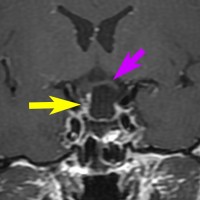

典型的なMRIの画像です

下垂体腺腫のMRIです。両側の視野障害(両耳側半盲)のために手術を受けた患者さんのものです。この腫瘍は非機能性腺腫といってホルモンを出さない腫瘍でした。少し大きめでしたが全部取れて視野の障害はよくなりました。

左の2枚はガドリニウム造影剤を使って写したもので腫瘍の形がよくわかります。右の1枚はT2強調画像と言います。MRIでは撮影の仕方によって見え方が違います。

日本で汎用されているものでは最も解像力が高い3テスラMRIで撮影された,ガドリニウム増強像です。左側の画像では下垂体の大きさと形は正常に見えます。画像を調整すると,下垂体の内部,右端(黄色の矢印の先)に6mmくらいの小さな腺腫がみつかりました。MRIの性能がよくなったことによって数mmの小さなものも診断できるようになりました。